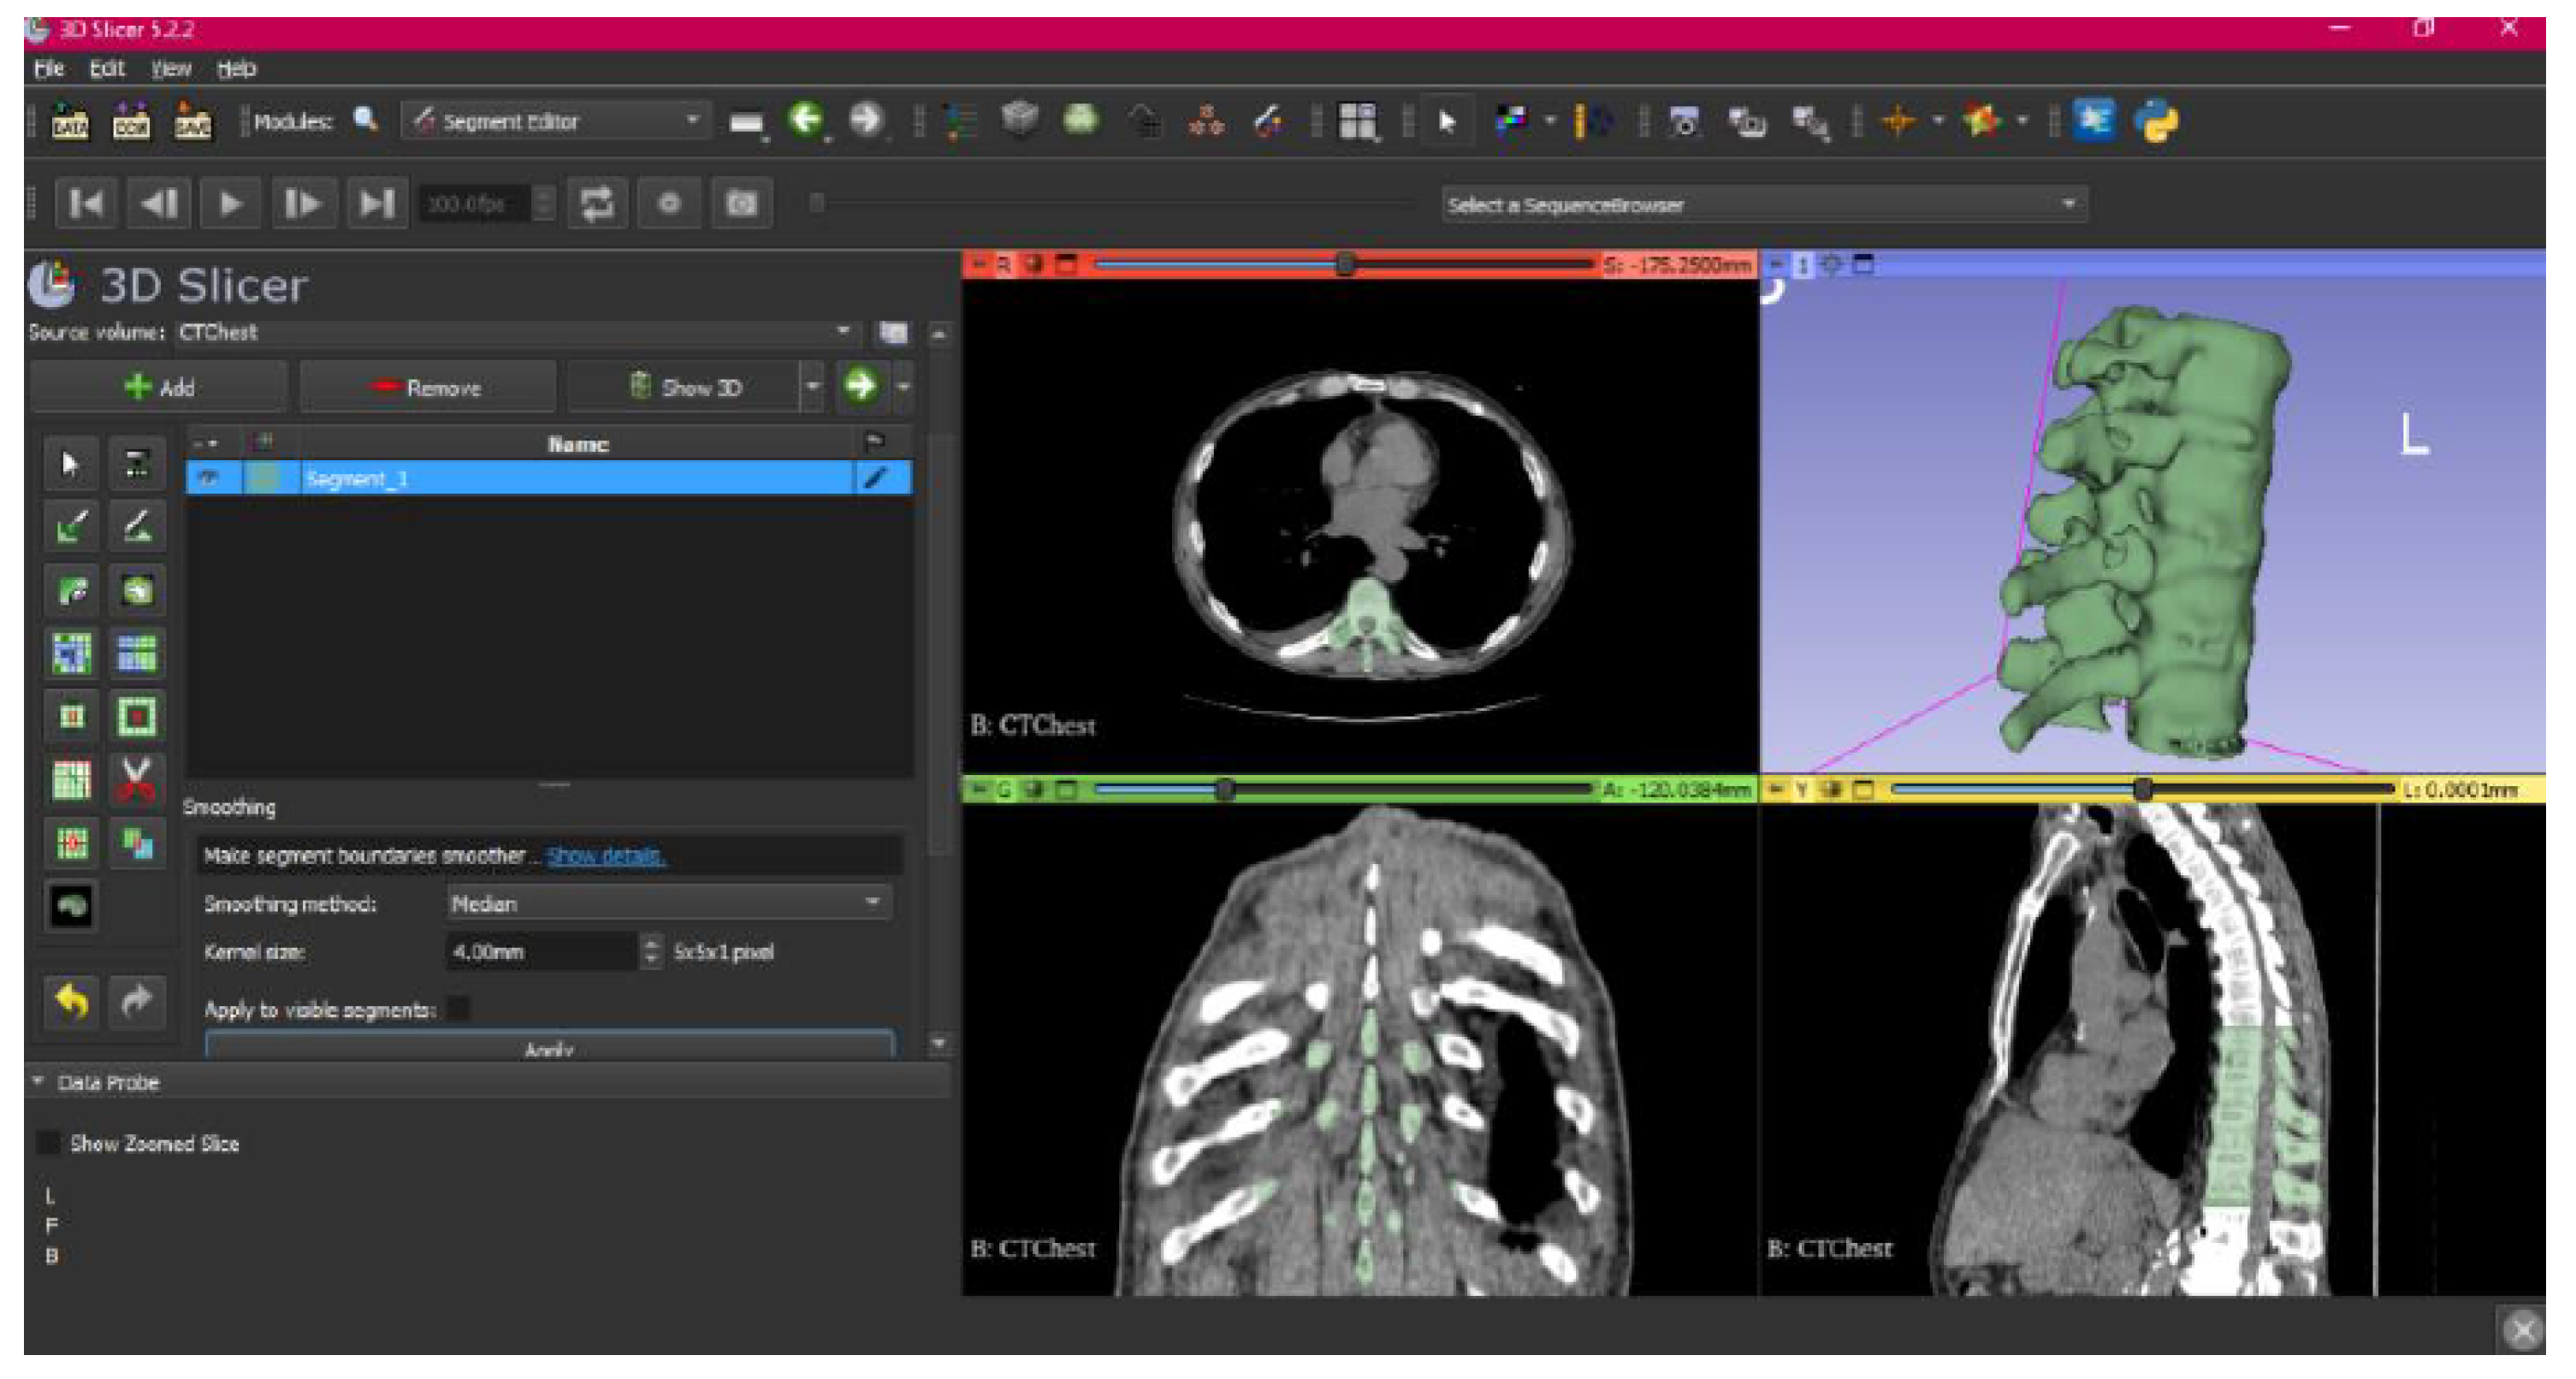

- Select the “Smoothing” tool.

- Choose the “median” or “mean” method, and configure the kernel size as needed.